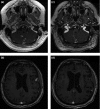

Figures